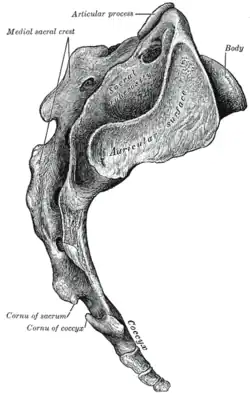

Cóccix

O cóccix (pronuncia-se "cók-sis"[1]) é um pequeno osso da parte inferior da coluna vertebral restante do que antes se integrava a cauda. É constituído por quatro vértebras coccígeas, soldadas entre si, sendo as inferiores progressivamente menores. A vértebra superior apresenta uma faceta elíptica que se articula com o sacro. Atrás desta localizam-se duas saliências verticais denominadas pequenos cornos do cóccix. De cada lado encontram-se dois prolongamentos transversais denominados grandes cornos do cóccix.

O cóccix articula-se com o sacro através dos seguintes ligamentos:

- O ligamento interósseo é uma fibrocartilagem localizada entre as respectivas superfícies articulares.

- O ligamento sacro-coccígeo posterior une a extremidade inferior da crista sagra às faces posteriores das 2ª ou 3ª vértebras coccígeas

- Os ligamentos sacro-coccígeos laterais são constituídos por dois feixes, um medial unindo o sacro aos pequenos cornos do cóccix, e outro lateral unindo o sacro aos grandes cornos do cóccix.